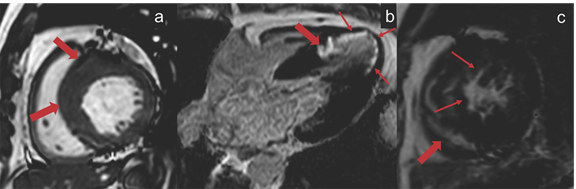

A 64-year-old man with no prior cardiac illness presented with typical angina with ST-T wave changes on electrocardiograph (ECG) and elevated cardiac troponins requiring emergent catheter angiogram which showed 95% stenosis in the mid left anterior descending artery (LAD) for which percutaneous coronary intervention was done (Figure 1). The ECG and 2D-transthoracic echocardiogram (TTE) also showed changes of asymmetric left ventricular hypertrophy with a significant outflow tract gradient consistent with obstructive HCM. As a part of the workup for HCM, the patient underwent a CMR imaging that revealed asymmetric thickened basal and mid septum (22 mm in end diastole), with relatively thinned out and hypokinetic left ventricular (LV) apex. There was subendocardial LGE along the LAD territory with midmyocardial enhancement involving the hypertrophied septum (Figure 2).

Figure 1 Coronary angiogram of the left coronary system in cranial right anterior oblique projection showing ~95% stenosis in the mid segment of left anterior descending artery (arrowhead). (B) Coronary angiogram of the left coronary system in cranial right anterior oblique projection after successful stenting of mid left anterior descending artery with a 3.5 x 38 mm drug eluting stent. A coronary wire is seen in situ.